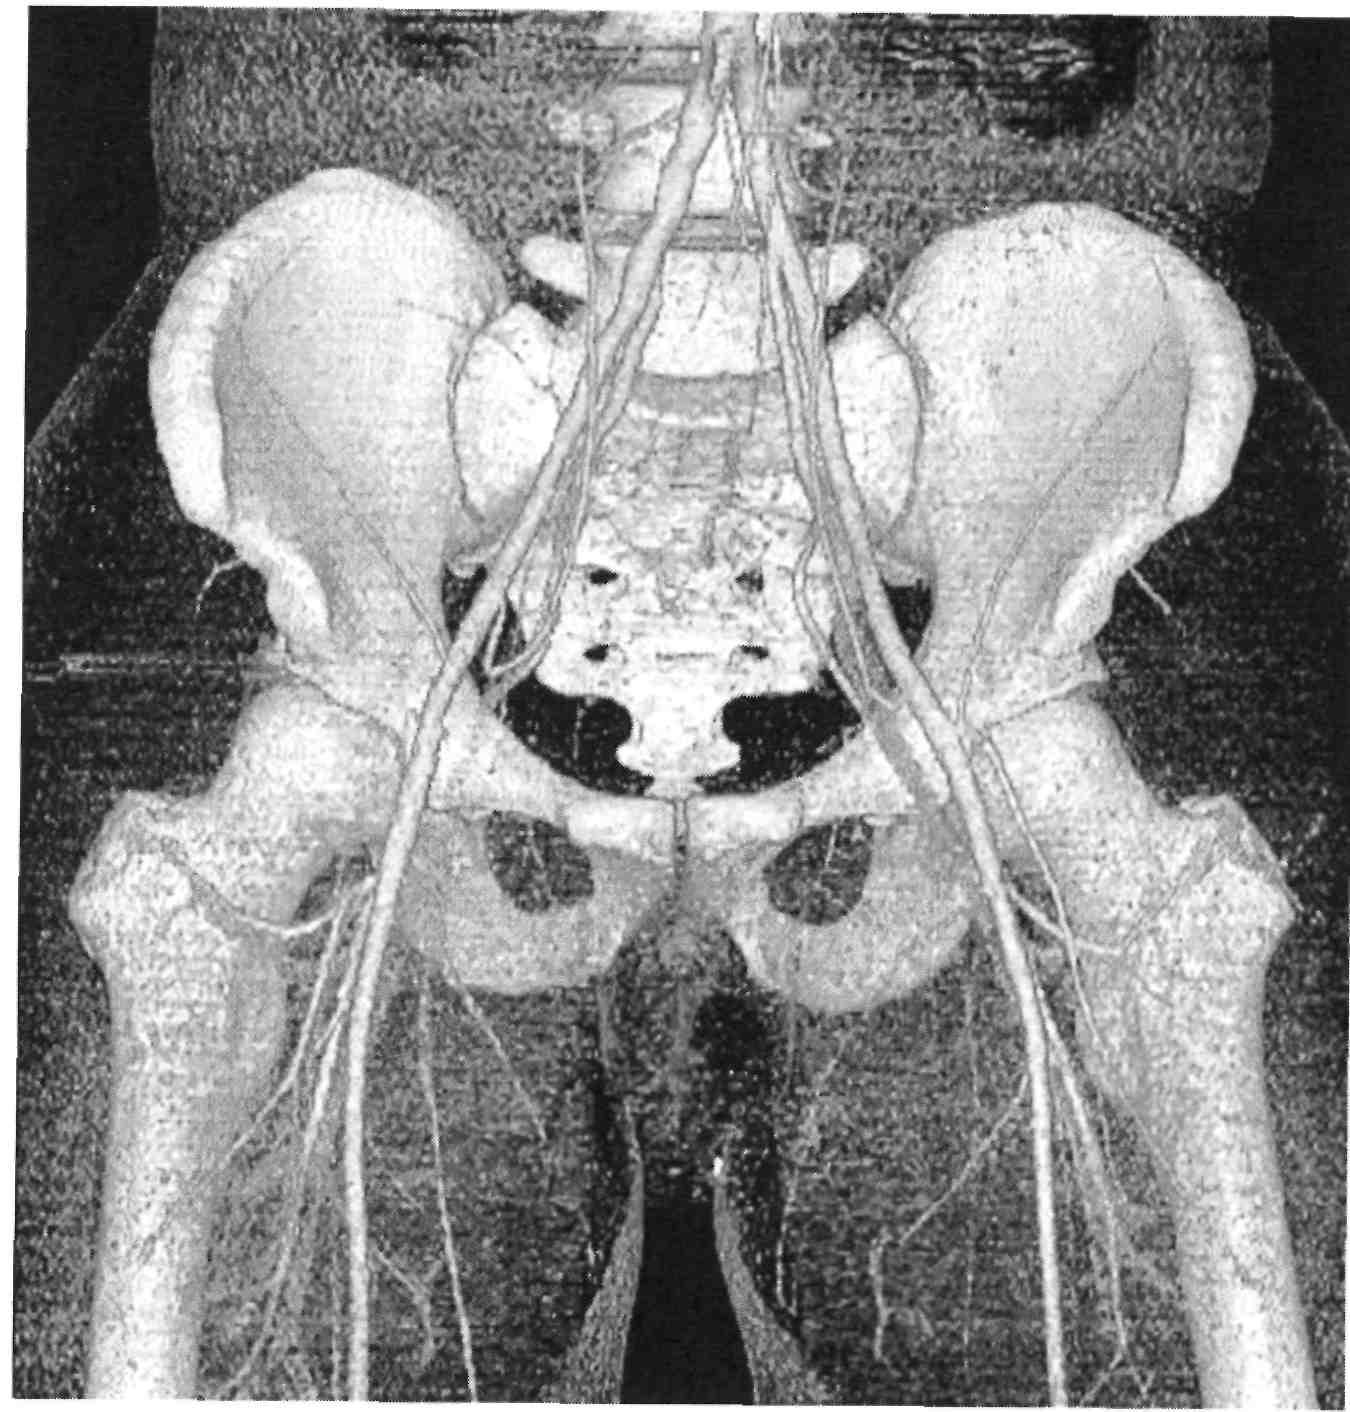

Компьютерная томография органов малого таза: оборудование и результаты исследований